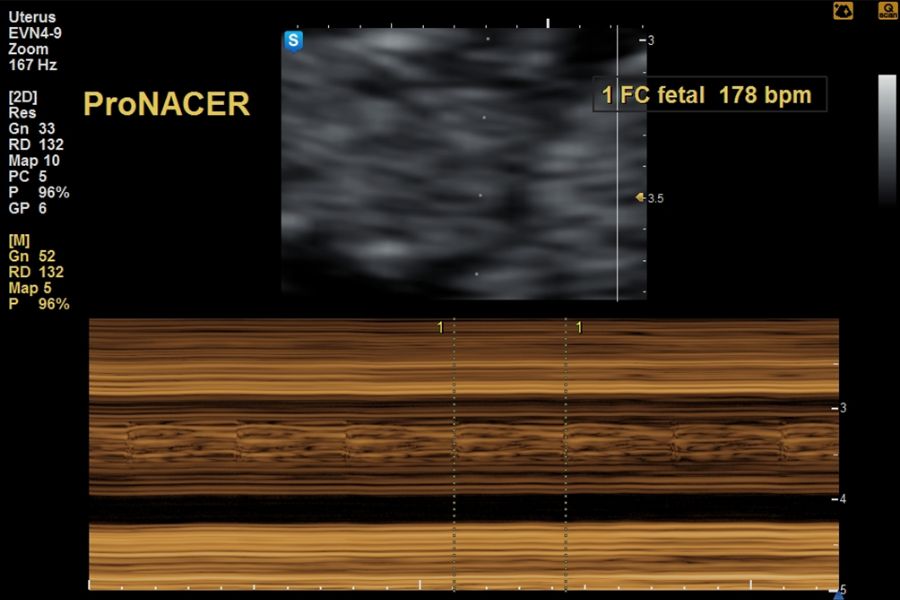

Ecografía de viabilidad desde las 6 a 10 semanas